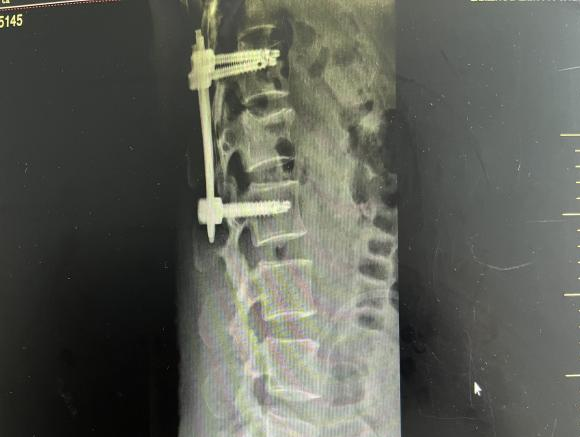

12月17日,贵州航天医院第88次晨读会由我院骨一科主任、副主任医师陈明勇作学术交流,他以“肱骨近端骨折并肩关节脱位的手术治疗”为题,全面讲解了该损伤的手术策略、术中血供保护理念及内侧支撑重建技术等内容,并通过多个典型病例图文资料分享了从损伤机制分析、手术步骤实施到术后随访评估的完整过程与关键细节,为临床处理此类复杂骨折提供了较为全面的技术参考,有助于在手术规划中结合个体情况开展针对性治疗。 贵州航天医院 骨科专家简介 陈明勇 骨一科主任,副主任医师 临床擅长:从事创伤骨科工作约20年,对骨缺损、骨不连、骨肿瘤、肢体畸形等的肢体矫形重建及功能重建,慢性化脓性骨髓炎的根治治疗、糖尿病足的保肢治疗、快速康复理念(ERAS)下的老年骨折的诊治,四肢复杂骨折的诊治,四肢骨折等微创手术治疗具有丰富的临床经验。 2004年毕业于遵义医学院临床专业,曾在中国人民解放军总医院、广西医科大学第一附属医院、上海第六人民医院骨科进修。中国中西医结合学会骨伤科专业委员会横向骨搬移治疗糖尿病足及微血管网再生学组首届委员,遵义市医学会创伤分会常务委员。 瞿 晖 骨科党支部书记,骨二科主任,副主任医师 临床擅长:对骨科的常见病、关节外科、脊柱外科及运动医学疾病的诊治具有丰富的临床经验,熟练掌握骨科手术操作技术。 毕业于遵义医学院临床医学系,2005年前往广州中山大学第一附院骨显微医学部进修学习,2011年前往成都华西医院进修学习,并多次在省内外学习骨科相关知识,是中华医学会骨科分会会员。 赵小锋 中共党员,骨二科副主任,副主任医师 临床擅长:从事骨科临床工作11年,对骨科常见病、多发病诊疗有较为丰富的临床经验,擅长脊柱相关疾病诊断及治疗,尤其是颈、腰、腿疼痛疾病诊断及治疗,擅长胸腰椎骨折微创经皮穿刺内固定术、经皮穿刺椎体成形术、经皮穿刺脊柱内镜下腰椎间盘摘除术、单纯开创腰椎间盘摘除术、腰椎滑脱复位椎间植骨椎融合内固定术、腰椎管狭窄减压融合内固定术及人工髋、膝关节置换术等。 2012年毕业于遵义医学院外科学专业硕士研究生,2019年参加“遵义市115医学人才精英计划”于上海交通大学第一附属医院培训学习,2023年于北京大学第三人民医院脊柱外科进修学习,曾获得遵义市优秀医师荣誉称号。 遵义市手外科第一届委员,遵义市医学会创伤分会第一届委员,遵义市医学会创伤分会第二届委员,贵州省康复医学会第三届脊柱脊髓专业会委员,遵义市医学会烧伤与整形外科学分会委员,发表论文5篇,其中国家级核心期刊1篇,SCI论文1篇,主持市级课题1项并结题,参与市级课题2项。 赵兴东 骨科主任医师 临床擅长:擅长骨科的常见病及各种创伤、四肢骨折创伤修复、骨感染、手足疾病的诊治和手足体表畸形的矫形整复,熟练掌握骨科四肢骨病及创伤的手术操作技术,尤其在四肢关节复杂性损伤、手足外伤、组织缺损创面、难治创面的皮瓣修复方面及平足、高弓足矫形方面及四肢慢性疼痛诊治、康复方面具有丰富的临床经验。 硕士研究生,毕业于遵义医学院临床外科系,2015年前往山东省立医院手足外科进修学习;遵义市医学分会创伤分会第一、二届委员,遵义市手外科医学会第二委届员会常务委员;在省级及省级以上期刊发表文章9篇,参编著作2部,参与主持并完成市级课题1项,参与市级课题2项、省级课题1项。 张艳金 中共党员,骨科副主任医师 临床擅长:从事骨外科工作16年,对复合伤、多发伤的救治、四肢骨干骨折、关节周围骨折、骨肿瘤、骨髓炎等诊治具有丰富的临床经验。 中共党员,硕士研究生,2006年本科毕业于山西医科大学第二临床医学院,2011年研究生毕业于北京军区总医院;在“老年COPD患者合并髋部骨折的诊治”国际合作课题组研究两年,在老年髋部骨折的诊治方面具有丰富的经验,并发表论文6篇;主持遵义市级课题1项,承担遵义医科大学的临床教学工作,获得遵义医科大学优秀带教老师荣誉。编撰有《骨科疾病诊疗精粹》一书,开展2项新技术,编撰地方规范《务川自治县创伤骨科常见疾病诊疗规范》一书。 张俊凯 骨科副主任医师 临床擅长:从事骨科临床工作28年,对创伤骨折、骨感染、骨缺损、骨不连等外科诊治,四肢骨折的微创手术治疗,四肢复杂骨折(如关节内粉碎性骨折、多发骨折等)的损伤控制及手术治疗等具有丰富的临床经验。 1995年毕业于遵义医学院临床专业,2009年前往复旦大学附属医院骨科进修1年。 卢懿明 中共党员,骨科副主任医师 临床擅长:从事骨科工作18年,对创伤骨折、四肢骨折的微创手术治疗、四肢复杂骨折(如关节内粉碎性骨折、多发骨折等)的损伤控制及手术治疗,尤其是髋部骨折的PFNA等微创技术,踝关节骨折、膝关节周围骨折的Mipo微创技术等具有丰富的临床经验,开展了4项新技术,发明6项新型专利技术。 2005年毕业于遵义医学院临床专业,2017年,前往南方医科大学第三附属医院骨科进修半年,回院后运用Mipo技术对骨干骨折及干骺端骨折的治疗技术,同时积极开展骨盆骨折、髋臼骨折腹直肌外侧切口的应用;发表了多篇专业论文,经常参与省内外学术交流会授课,获得医院荣誉称号多个。 邬夏荣 骨科副主任医师 临床擅长:从事骨科工作16年,对四肢复杂骨折、骨肿瘤的诊治,尤其是足踝创伤、慢性踝关节损伤、平足症等诊疗具有丰富的临床经验。 2006年毕业于遵义医科大学临床医学专业,曾在陆军军医大学西南医院进修学习,发表多篇骨科学术论文。 余德怀 中共党员,骨科副主任医师 临床擅长:从事骨科工作10余年,对运动医学、骨关节、脊柱外科常见病、多发病的诊治具有丰富的临床经验。 硕士研究生,2011年毕业于遵义医学院临床医学专业,曾前往遵义医科大学附属医院运动医学专业进修学习;是贵州省医学会运动医学分会青年委员,西部关节镜联盟委员;发表多篇骨科学术论文。 冯 乾 骨科副主任医师 临床擅长:从事骨科工作近20年,熟练掌握骨科多发病及常见病的诊治,尤其对脊柱退变性疾病的诊断及治疗具有丰富的临床经验,主要研究脊柱微创相关治疗方式,能熟练开展椎间孔镜及UBE。 曾前往北京大学第三医院进修学习疼痛及椎间孔镜、首都医科大学友谊医院专业进修脊柱内镜;是贵州省康复医学会第三届脊柱脊髓专业委员会委员;发明专利3项、发表脊柱外科专业论文多篇。 贵州航天医院骨科简介 基本情况 贵州航天医院(原3417医院)骨科组建于1968年,前身是以创伤和断肢(断指)再植闻名于世的上海市第六人民医院骨科,中国断肢(断指)再植的奠基者、中科院院士陈仲伟等专家莅临科室指导医疗和教学,并在70年代开展了贵州省首例断肢(断指)再植手术。组建50余年来,诊治患者已逾百万,挽救了无数的伤病员,成为了保障遵义地区人民群众健康的重要支撑。 经过几代人的不懈努力,今天的骨科,已由创伤骨科发展至骨病、骨肿瘤、骨结核等领域,现有脊柱外科、关节外科、四肢创伤、手足外科四个亚专科,成为了集医疗、教学、科研于一体的综合学科,是贵州省临床重点专科、遵义市临床重点专科、遵义市骨科临床医学中心、遵义市基层骨科专科联盟理事长单位。 科室目前开放床位110张,共有医护人员50余人,副高级以上专家18人,硕士研究生15人。拥有一流骨科医疗设备多台,每年不定期选派优秀技术骨干到全国各大知名医学院校进修、学习、参观、交流,并邀请国内、国外知名专家教授来院进行交流、指导,通过不断引进国内外先进的诊疗技术,科室医疗技术水平稳步提升,为广大人民群众提供了优质的医疗服务。 专科特色 骨一科 (一)骨缺损、骨不连的肢体与功能重建 胫骨横向骨搬移技术治疗糖尿病足: (二)慢性骨髓炎的根治治疗 (三)肢体缺血性疾病如糖尿病足、脉管炎的保肢治疗 (四)皮瓣修复 (五)复杂创伤的治疗 (六)老年髋部骨折及小儿骨折快速手术 老年髋部骨折: 骨二科 (一)胸腰椎骨折微创经皮椎弓根螺钉固定术 (二)老年性骨质疏松性患者腰椎滑脱脊柱内固定术(骨水泥螺钉) (三)V形双通道脊柱内镜技术(VBE)腰椎融合术治疗腰椎退行性疾病 (四)老年性骨质疏松性骨折(PVP/PKP)术 (五)人工髋关节置换术 (六)双侧股骨头坏死人工全髋关节置换 (七)右侧全髋置换术后假体周围骨折翻修 (八)人工膝关节置换术 (九)人工膝关节假体松动翻修 (十)关节镜技术 传统手术切口 关节镜技术切口 诊疗范围 骨一科 1.四肢创伤、矫形。 2.手、足踝外科。 骨二科 end